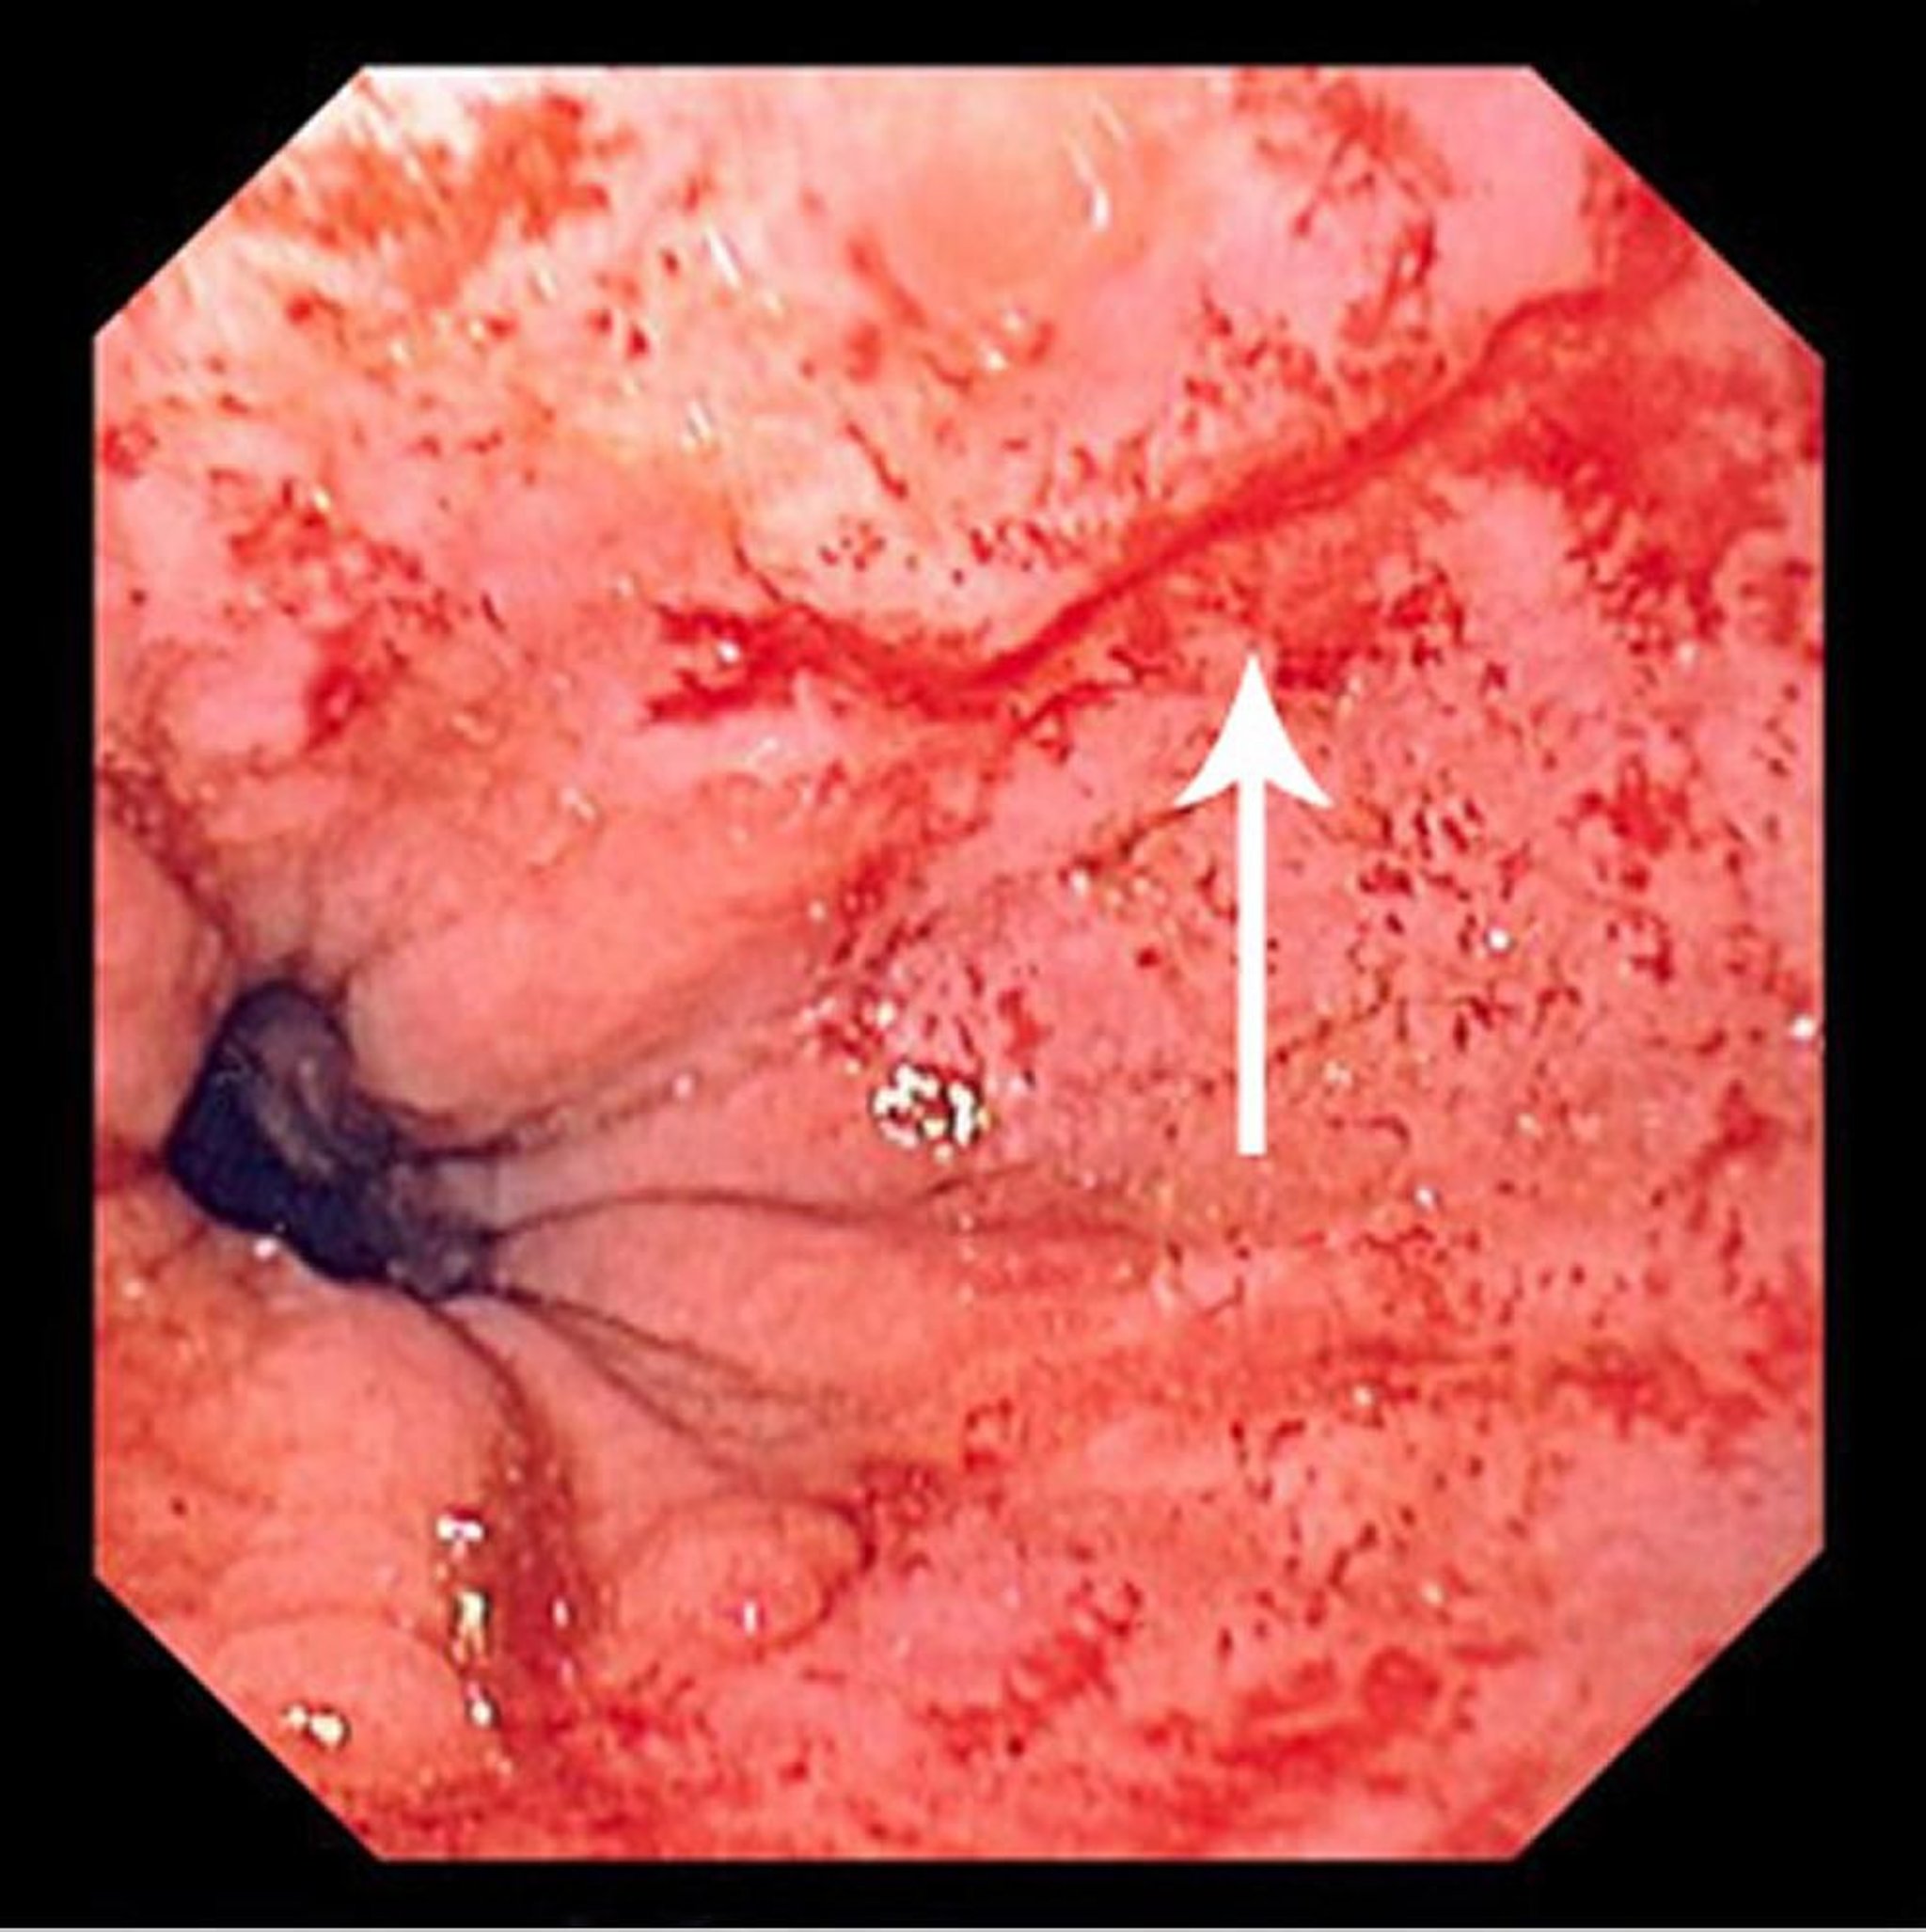

Desgarro de Mallory-Weiss

Esta imagen muestra un desgarro lineal delgado (flecha) que comienza inmediatamente por encima de la unión escamocilíndrica y se extiende en dirección proximal.

Image provided by David M. Martin, MD.